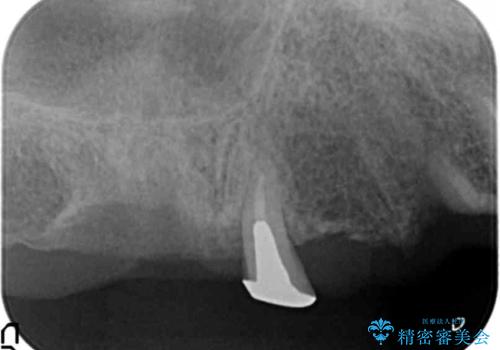

保存可能な2本の歯を用いて、マグネットデンチャー(磁性アタッチメントを用いた入れ歯)による治療を行いました。

- ¥780,000 (根管治療×2本、土台×2本、磁性アタッチメント×2、金属床義歯)費用は治療当時の料金となります

予算を抑えて審美的に咬合を回復することができ、ご満足頂けました。

マグネット(磁石)により入れ歯がはずれにくく動揺しにくいため、入れ歯安定剤などを使うことなく食事やお話も問題なくできると喜んで下さいました。